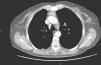

Case ReportIn May 2007, a 54-year-old woman with an important smoking history was referred to us due to an adenocarcinoma of the right lower lobe associated with a paraneoplastic syndrome (Pierre Marie Bamberg syndrome). At that time, she was found to have increased serum levels of carcinoembryonic antigen (CEA) (34ng/dl). Right lower lobectomy was carried out along with resection of the hilar and mediastinal lymph nodes by means of thoracotomy, which preserved the muscles of the right hemithorax. Three months after the surgery, we documented the complete regression of the paraneoplastic syndrome with the normalization of CEA serum levels (4ng/dl). The anatomic pathology evaluation of the samples confirmed a lung adenocarcinoma in stage pT2aN0. In the post-operative period, total body computed tomography (CT) was done every 6 months. In June 2009, a small solid lesion was found in the anterior mediastinum (max. diameter 1.8cm), while the serum levels of CEA continued to be normal and with the absence of paraneoplastic syndrome. In December 2009, CT revealed that the lesion in the anterior mediastinum had increased in size (max. diameter 3cm); with the administration of a contrast medium, the lesion was seen to be inhomogeneous, with a necrotic center (Fig. 1). No other intrathoracic or systemic lesions were seen. Serum CEA levels continued to be normal with absence of paraneoplastic syndrome. Positron emission tomography (PET)–CT demonstrated a lesion with the uptake of 18F-fluorodeoxyglucose-avid (maximal standardized uptake value 6.2). A thymic tumor was suspected, and thymectomy with en bloc resection of the tumor was carried out by means of cervicotomy and resection of the sternal manubrium.